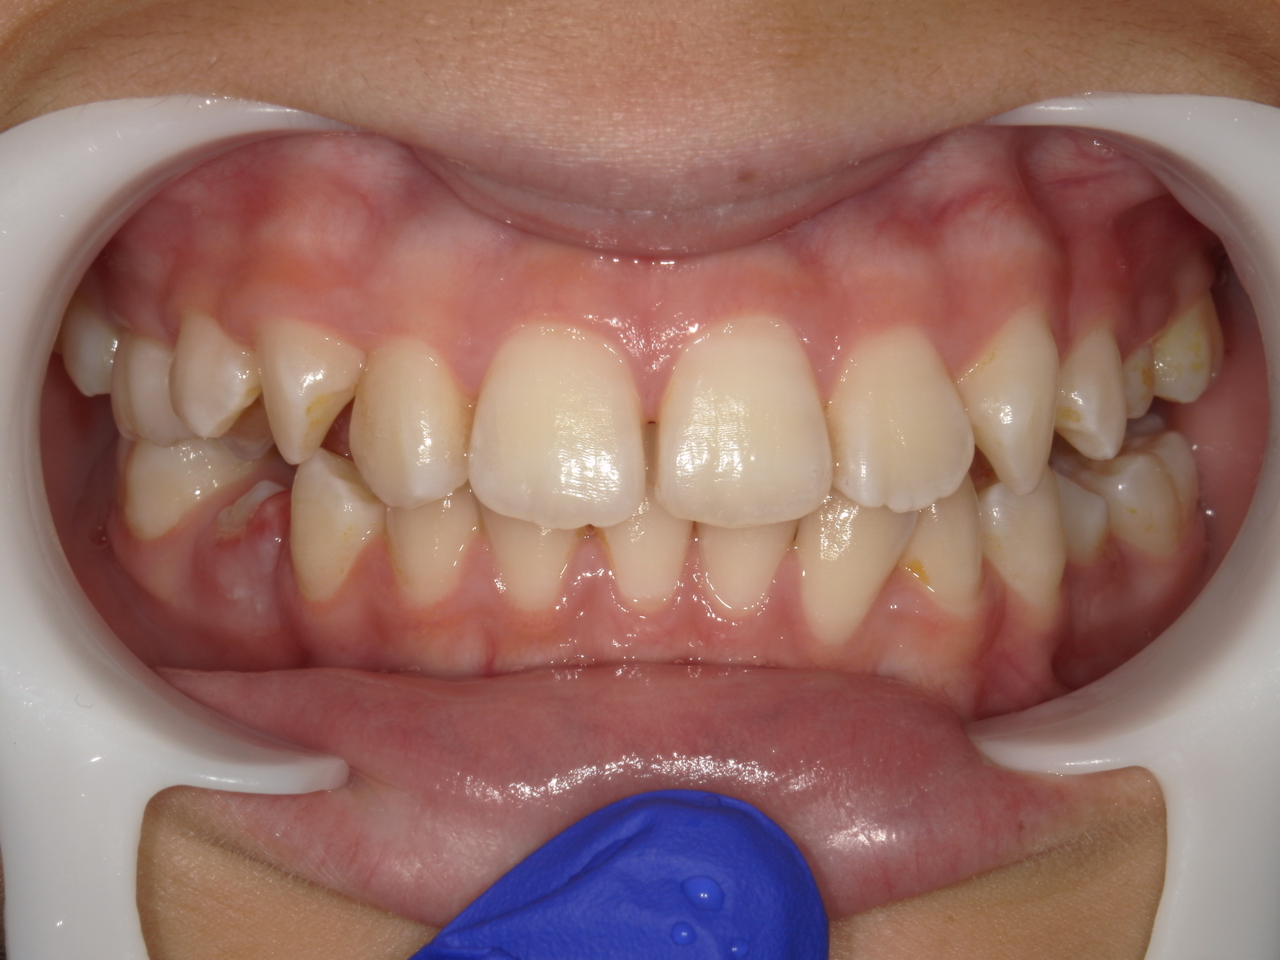

治療前

治療説明 歯科矯正で取り外し可能な矯正方法である床矯正で治療しました

治療期間 2年1か月

治療費200000 円

治療後

治療の副作用(リスク)歯の動き方には個人差があり、予想された治療期間が延長する可能性があります。。床矯正の使用状況、矯正歯科治療には患者さんの協力が必要であり、それらが治療結果や治療期間に影響します。2次矯正が必要になる場合もあります。